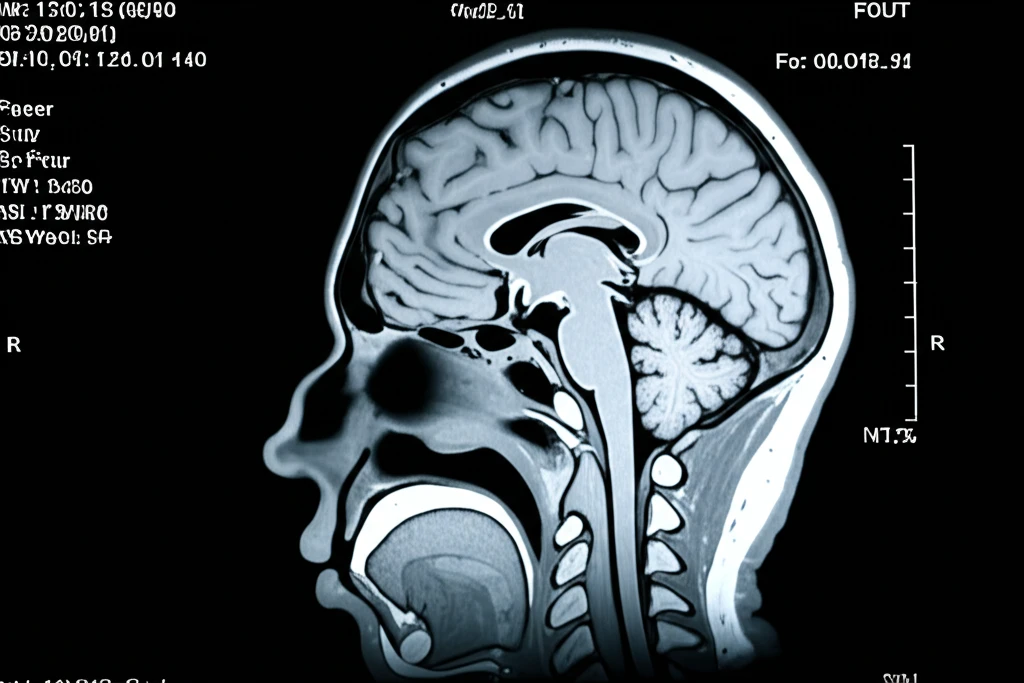

정확한 진단을 위한 첫걸음, 이비인후과 MRI 검사

이비인후과 질환은 다양한 원인으로 발생하며, 효과적인 치료를 위해서는 정확한 진단이 매우 중요합니다. 자기공명영상(MRI)은 뛰어난 연조직 대조도를 제공하여 이비인후과 영역에서 핵심적인 진단 도구로 자리매김했습니다. 특히, 복잡한 해부학적 구조를 가진 이비인후과 질환 진단에 MRI는 매우 유용하며, 수술 계획 수립 및 치료 방향 결정에 중요한 정보를 제공합니다. 이 글에서는 이비인후과 MRI 검사의 필요성, 검사를 통해 얻을 수 있는 정보, 검사 과정 전반에 대해 자세히 알아보겠습니다.

MRI는 뛰어난 연조직 해상도를 바탕으로 이비인후과 질환 진단에 매우 효과적이며, 특히 다음의 경우에 필요성이 강조됩니다.

X선이나 CT 검사로는 확인하기 어려운 작은 병변이나 복잡한 구조물도 MRI를 통해 선명하게 관찰할 수 있으며, 방사선을 사용하지 않아 안전하게 검사를 진행할 수 있다는 장점도 있습니다.